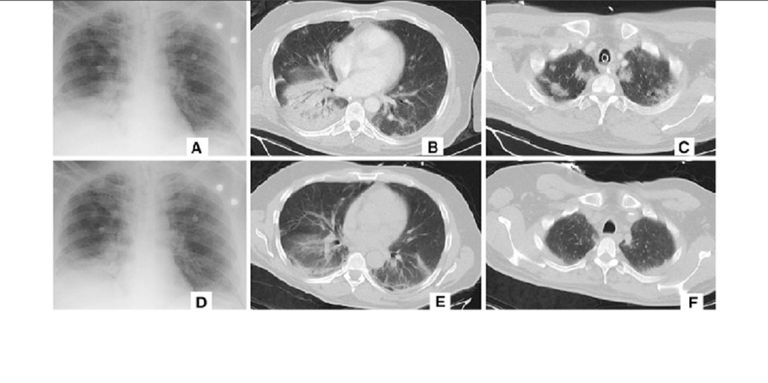

وطّورت "علي بابا" تقنية الذكاء الاصطناعي، ليكون قادراً على تحليل الصور التي التقطتها الماسح الضوئي وتحديد النقاط المثيرة للاهتمام، ومناطق الإصابة.

ومن خلال 5 آلاف وبيانات أخرى من السجلات الطبية لمرضى ووهان، تمكن المهندسون الصينيون من تدريب نظام الذكاء الاصطناعي لديهم لتعليمهم اكتشاف آثار عدوى فيروس "كورونا المستجد" على وجه التحديد على الجهاز التنفسي عن طريق فحصه بالماسح الضوئي.

وتقول شركة "علي بابا" إن نظامها قادر الآن على تأكيد ما إذا كان الشخص مصابا بفيروس كورونا في أقل من 20 ثانية وبدقة 96% أم لا.